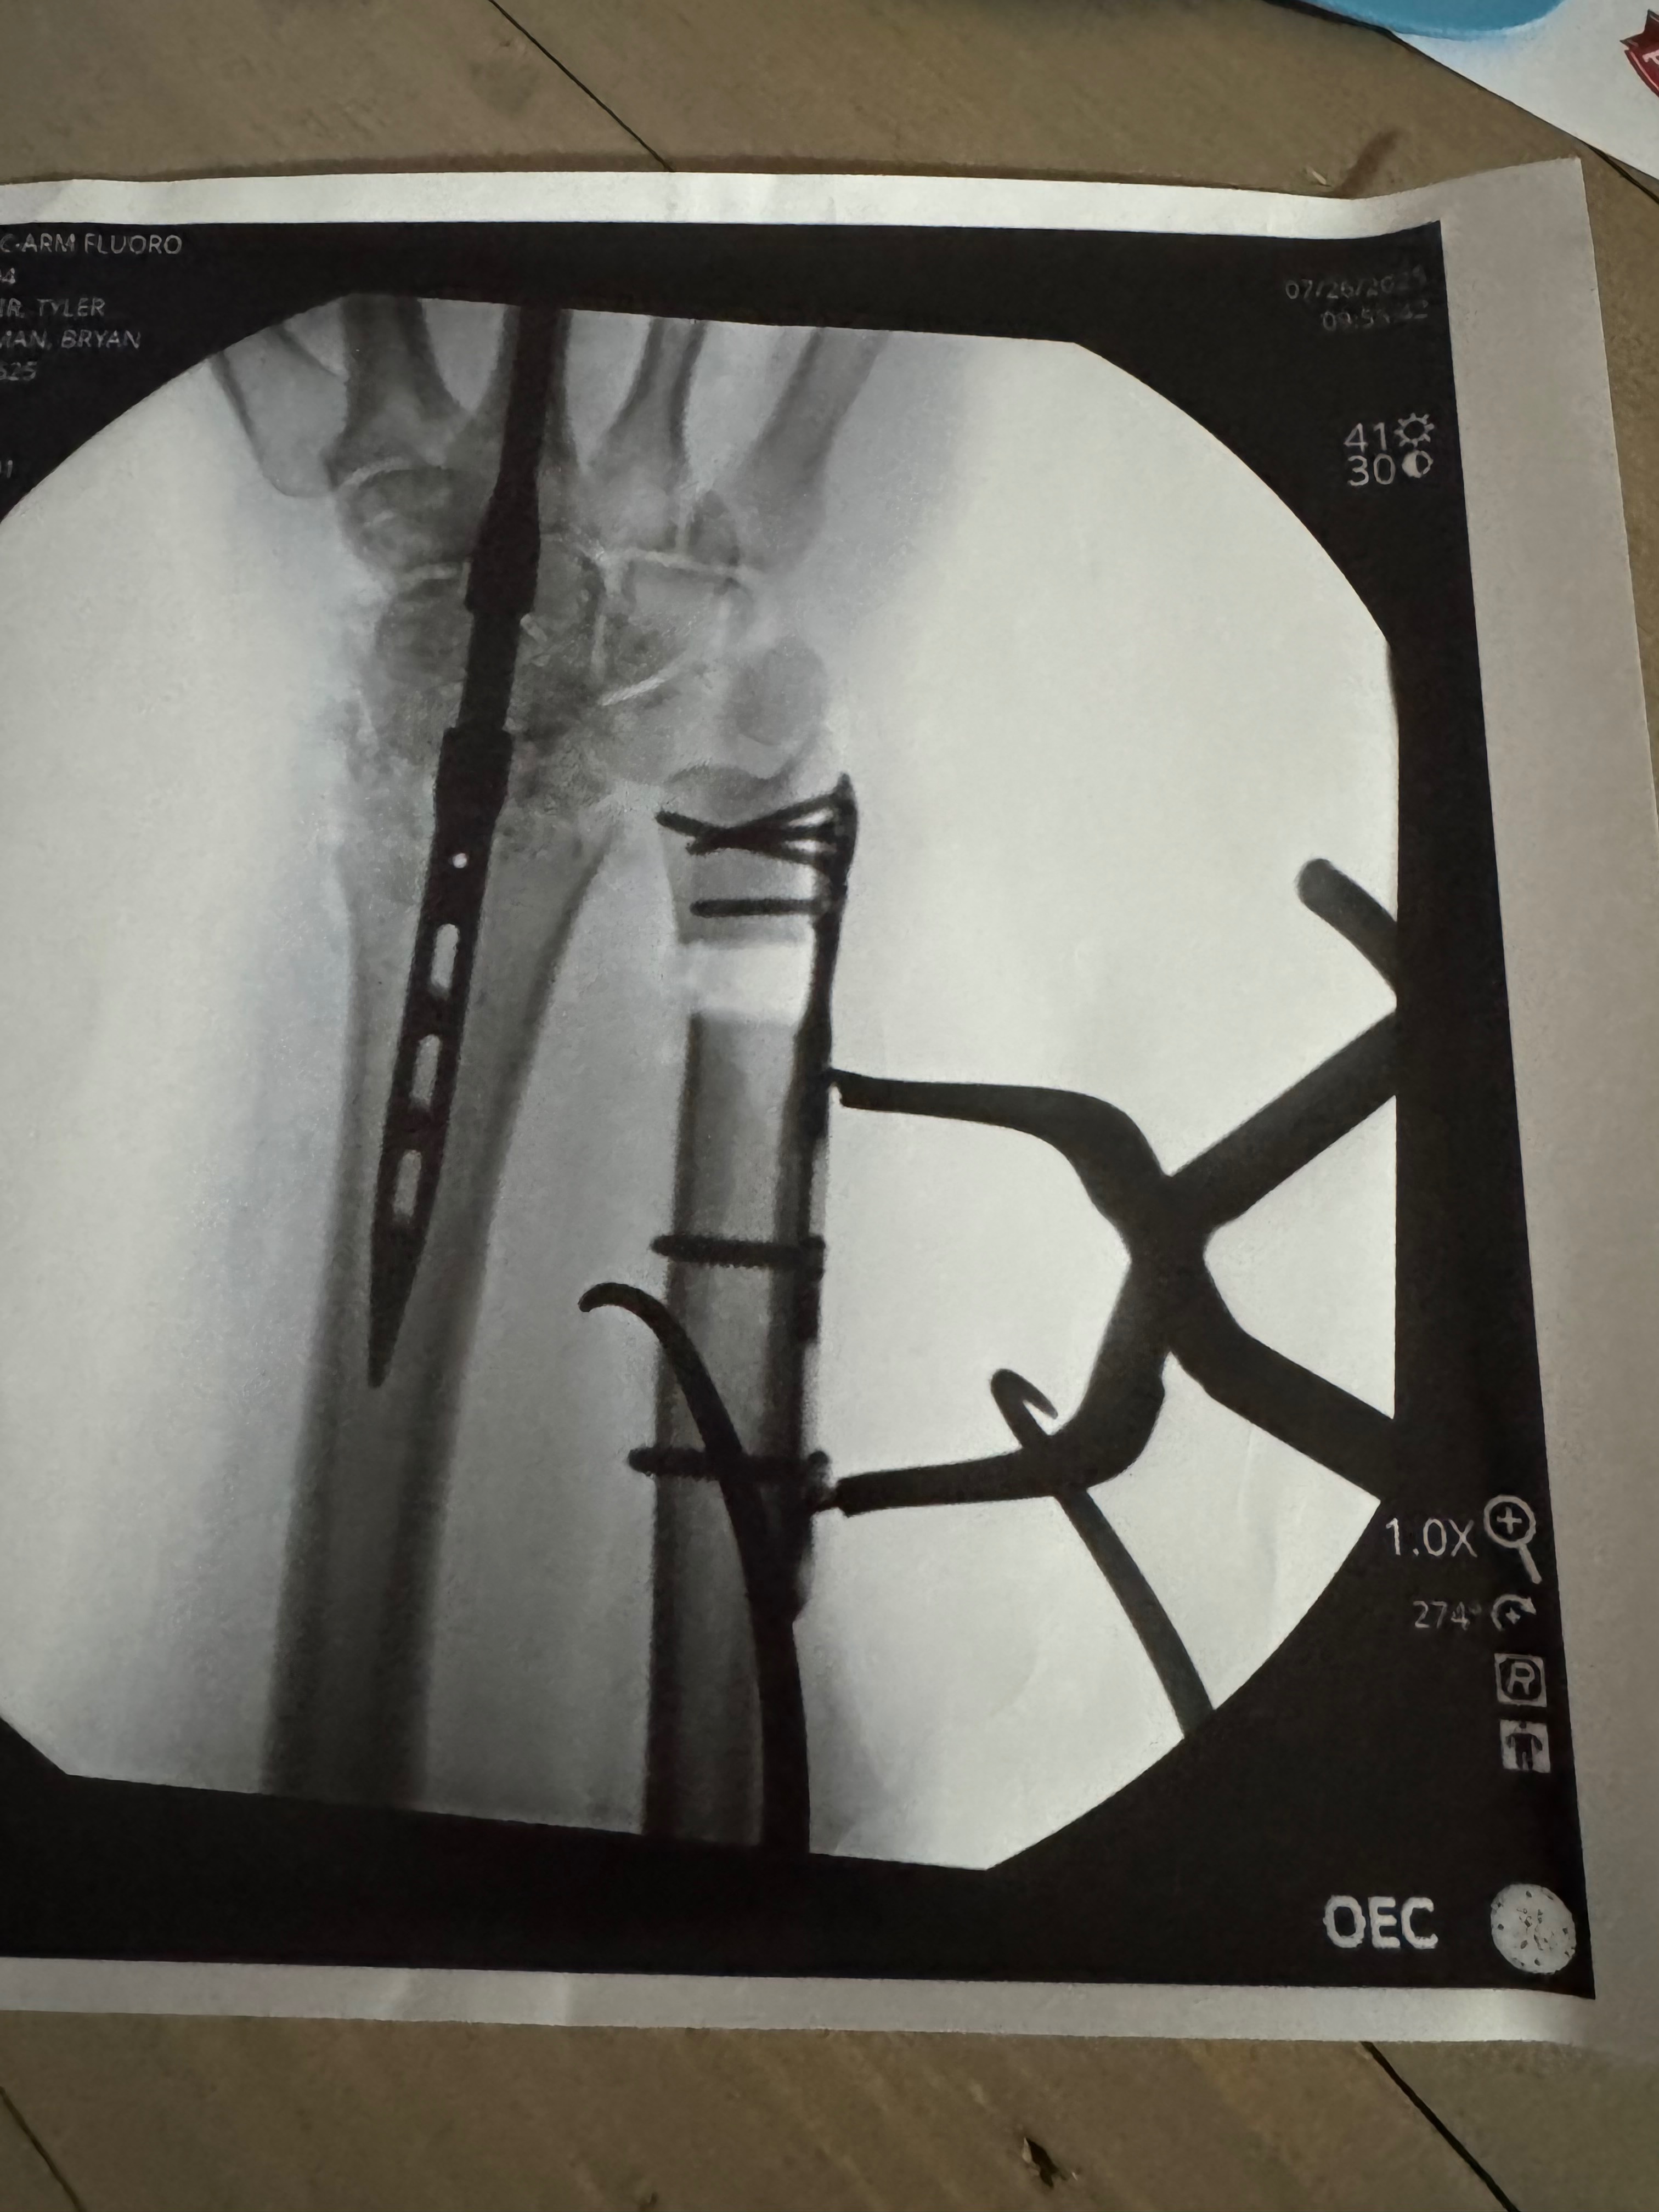

After spending three days in the hospital, I underwent an intense surgery on my wrist. The break was so severe that doctors had to perform a bone graft using my femur and permanently fuse a rod into my wrist. This means I will never regain full movement or bend my wrist again.